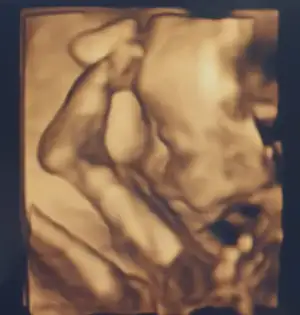

fotosunu da bırakayım günümüz şenlensin mi🥳🚀

Aa foto eklemeyi unutmuşum kızlarr😍

Bu da benim fındık kurdum😍🥳

Ayaklarını kafasının üstünde eliyle tutuyordu😅😅